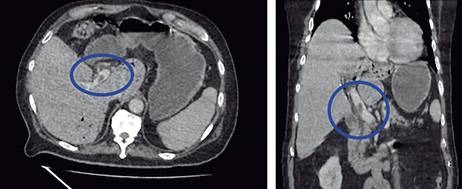

Masculino de 77 años con antecedentes de diabetes mellitus 2 e hipertensión arterial sistémica de larga evolución, antecedentes quirúrgicos de colecistectomía laparoscópica hace seis años y cateterismo cardiaco por cardiopatía isquémica crónica. Inicia su padecimiento actual 10 días previos a su ingreso con cuadro de dolor abdominal difuso en cuadrantes inferiores, así como ataque al estado general acompañado de astenia e hiporexia. Fue manejado por facultativo externo con antibioticoterapia. A su llegada al Servicio de Urgencias se presenta con taquicardia y tendencia a la hipotensión acompañado de alteración del estado de alerta. A la exploración física se palpa plastrón inflamatorio en cuadrante inferior izquierdo que despierta dolor a la manipulación del mismo, sin embargo, no hay datos de irritación peritoneal, sus laboratoriales con leucocitos 13,400 mm3, neutrofilia 92.9% y lactato de 3.9 mmol/l. Se solicita tomografía abdominopélvica contrastada en donde se muestra trombosis de la vena porta (Figura 1), neumatosis portal (Figura 2) y enfermedad diverticular (Figura 3), por los hallazgos anteriores se da manejo inicial con soluciones intravenosas y antibioticoterapia empírica de amplio espectro con piperacilina-tazobactam 4.5 g IV cada 8 horas, posterior al manejo estabilizador se realiza laparotomía exploradora, en donde se realiza sigmoidectomía y colostomía terminal debido a los hallazgos de perforación diverticular (Figuras 4 y 5) y plastrón inflamatorio purulento en el mesosigmoides con especial distribución en el trayecto de la vena mesentérica inferior, se toma cultivo y se maneja el posoperatorio en terapia intensiva, se deja antibioticoterapia dirigida a E. coli. Se calcula nutrición parenteral total y se inicia terapia anticoagulante con enoxaparina 60 mg subcutáneos (SC) cada 12 horas. El paciente cursó con evolución clínica favorable gracias al manejo multidisciplinario que se brindó. Egresó a la semana del procedimiento quirúrgico sin complicación alguna, se cita a consulta externa una semana después de su egreso tolerando vía oral con estoma funcional y con la herida afrontada. El reporte de histopatología reveló enfermedad diverticular complicada.